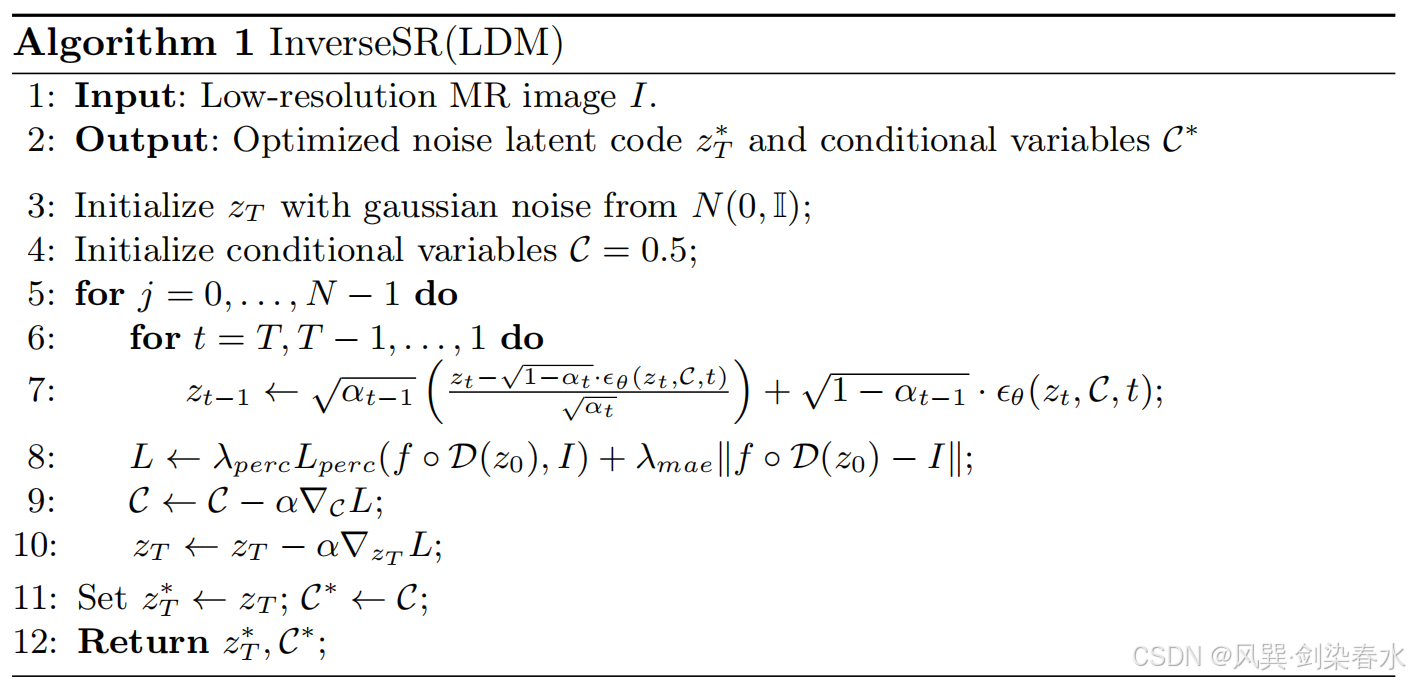

在高稀疏性 MRI SR 的情况下,优化噪声潜在编码 z T ∗ z_T^∗ zT∗ 及其相关条件变量 C ∗ \mathcal C^* C∗,以使用以下优化方法从给定的 LR 输入图像 I I I 中恢复 HR 图像:

其中 DDIM ( z T , C , T ) (z_T,C,T) (zT,C,T) 表示在 公式2 中对潜在编码 z 0 z_0 z0 进行的 T T T 个确定性 DDIM 采样步骤。遵循脑 LDM 模型,使用感知损失 L p e r c L_{perc} Lperc 和 L 1 L1 L1 像素级损失。损失函数是在生成模型和给定LR输入生成的被破坏图像上计算的,该方法的详细伪代码描述见 算法1。

(1)条件变量均初始化为 0.5,所有输入体积中的体素均归一化为 [0,1];

(2)DDIM 采样, T = 46 T = 46 T=46;(这个设置挺神奇)

(3)InverseSR(LDM), z T z_T zT 用随机高斯噪声初始化;

(5)在 InverseSR(LDM) 中使用了 600 步梯度下降,以确保收敛,InverseSR(Decoder) 中也使用了 600 步优化;

(6)使用 Adam 优化器, α = 0.07 α = 0.07 α=0.07, β 1 = 0.9 β_1 = 0.9 β1=0.9 和 β 2 = 0.999 β_2 = 0.999 β2=0.999;